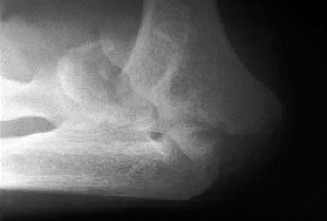

Imaging should include x-rays, which may demonstrate posterior glenoid bone loss or an impaction fracture on the anterior-superior humeral head (Fig. 2–38). CT images with 3D reconstructions can be very useful when assessing the extent of glenoid bone loss and evaluating glenoid and humeral version. Normal glenoid version is from −2 to −8 degrees of retroversion, and this may be increased in posterior instability. MRI can also be useful when assessing the posterior labrum (Fig. 2–39).

Figure 2–38 Radiographs showing a posterior shoulder dislocation.